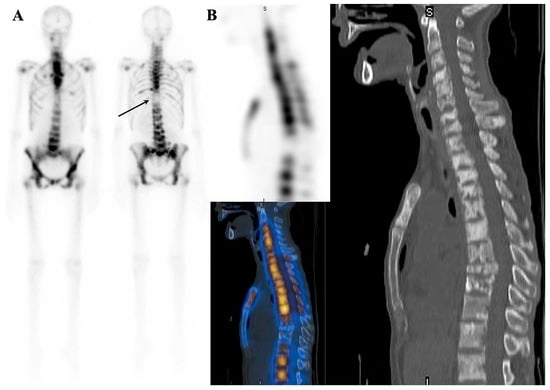

7.1.2. Dynamic Changes in Prostate Cancer Patients with Superscan

7.2. Metabolic Superscan